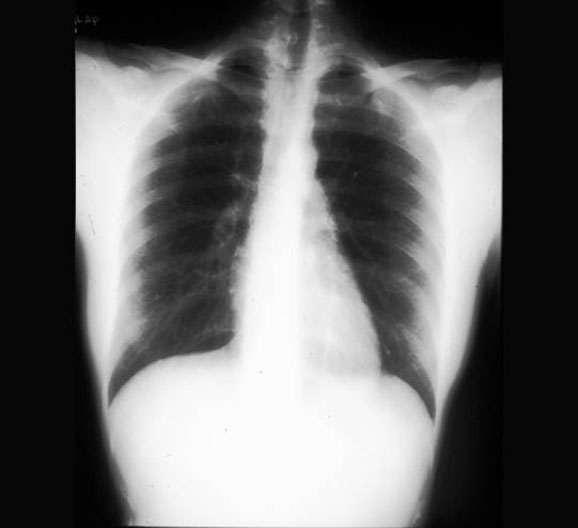

Chest X-Ray

Roll mouse over image to display labels.

1. Right lung

2. Heart

3. Right (acute) margin of heart

4. Diaphragm

5. Trachea

6. Left lung

7. Left (obtuse) margin of heart

8. Apex of Heart